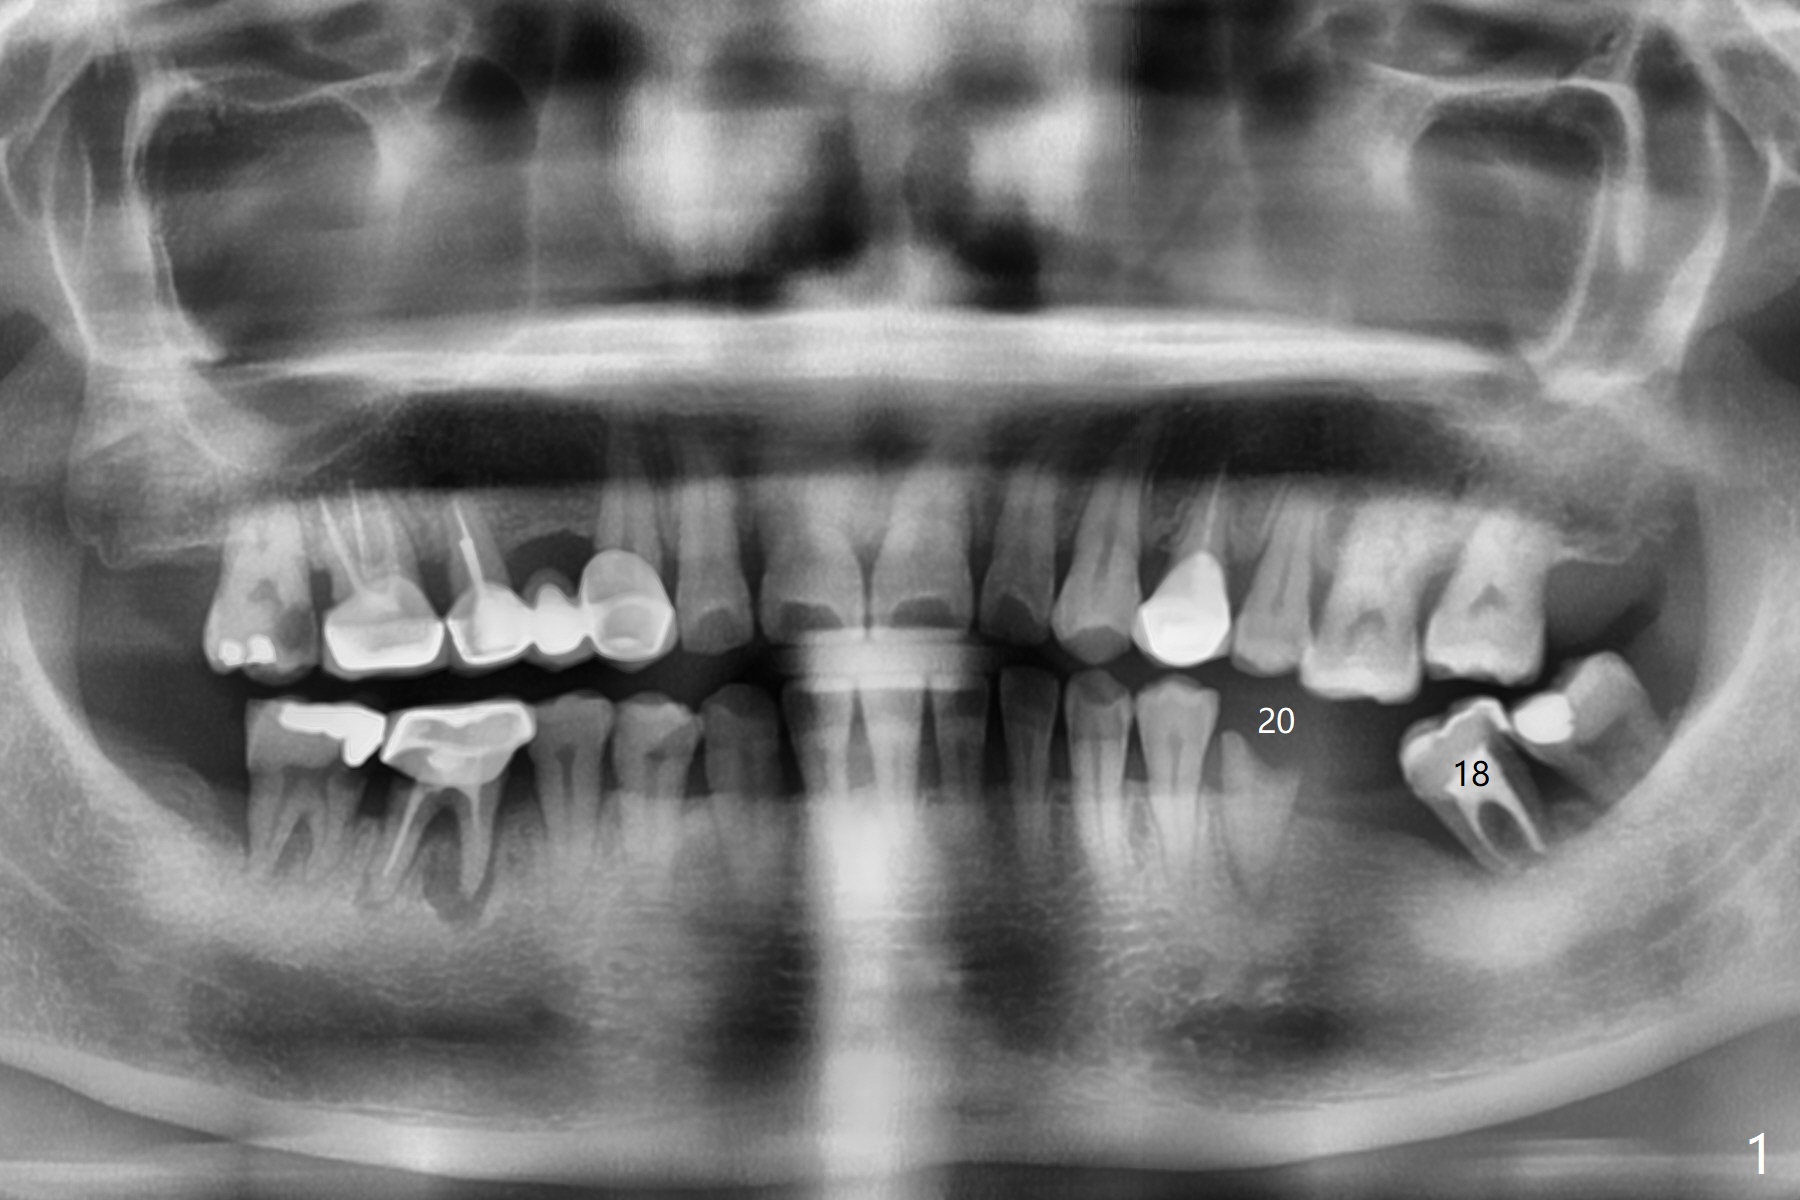

A 33-year-old woman fractures #20 equigingival with caries (Fig.1,2 barely salvageable). The ridge at #19 is atrophic (Fig.3), while the tooth #18 has mobility II (Fig.4). It seems that the best option would be extraction of #18 and 20 and immediate implant with guide (Fig.4). The tooth #20 is vital; socket shield will be conducted. To further prevent buccal plate collapse, a 3.5 or 4.0x10 mm implant will be placed lingual (Fig.2).